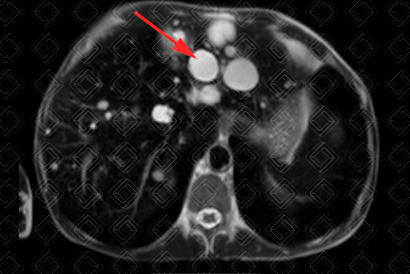

Texto alternativo para a imagem Figura 1. Créditos: Dra. Elazir Mota - Rio de Janeiro/RJ

Descrição das figuras 1 e 2: Ressonância magnética. Imagens ponderadas em T2 (sequência HASTE), plano coronal e axial, evidenciando imagens com contornos lobulados e alto sinal em T2, algumas com septos internos, dispersos pelo parênquima hepático (setas vermelhas).

• Ressonância magnética do abdome com contraste venoso: O cisto simples em geral é redondo, com sinal homogêneo, baixo em T1 e alto em T2. O contorno é regular e a parede imperceptível. Não há realce no estudo pós-contraste.